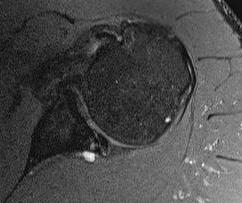

MRI

Spinoglenoid cyst

Spinoglenoid cyst with SLAP tear and posterosuperior labral tear